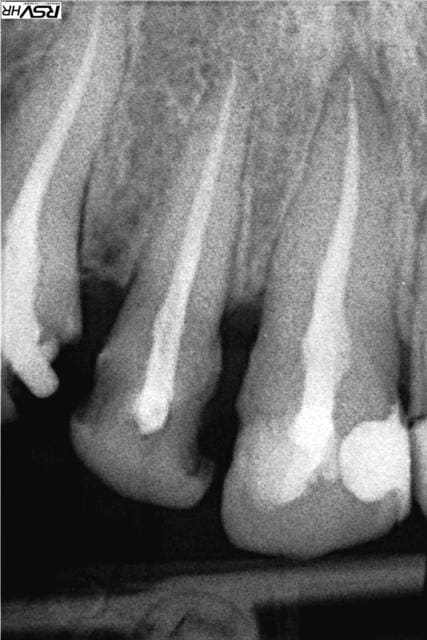

En PJ le dernier specimen, 28 ans, CMU mais dispo que le soir (ben oui il travaille au noir) la bouche en tchernobyl. Je n'ai fait que répondre à sa demande : des dents blanches devant. Pour les extractions allez voir ailleurs.